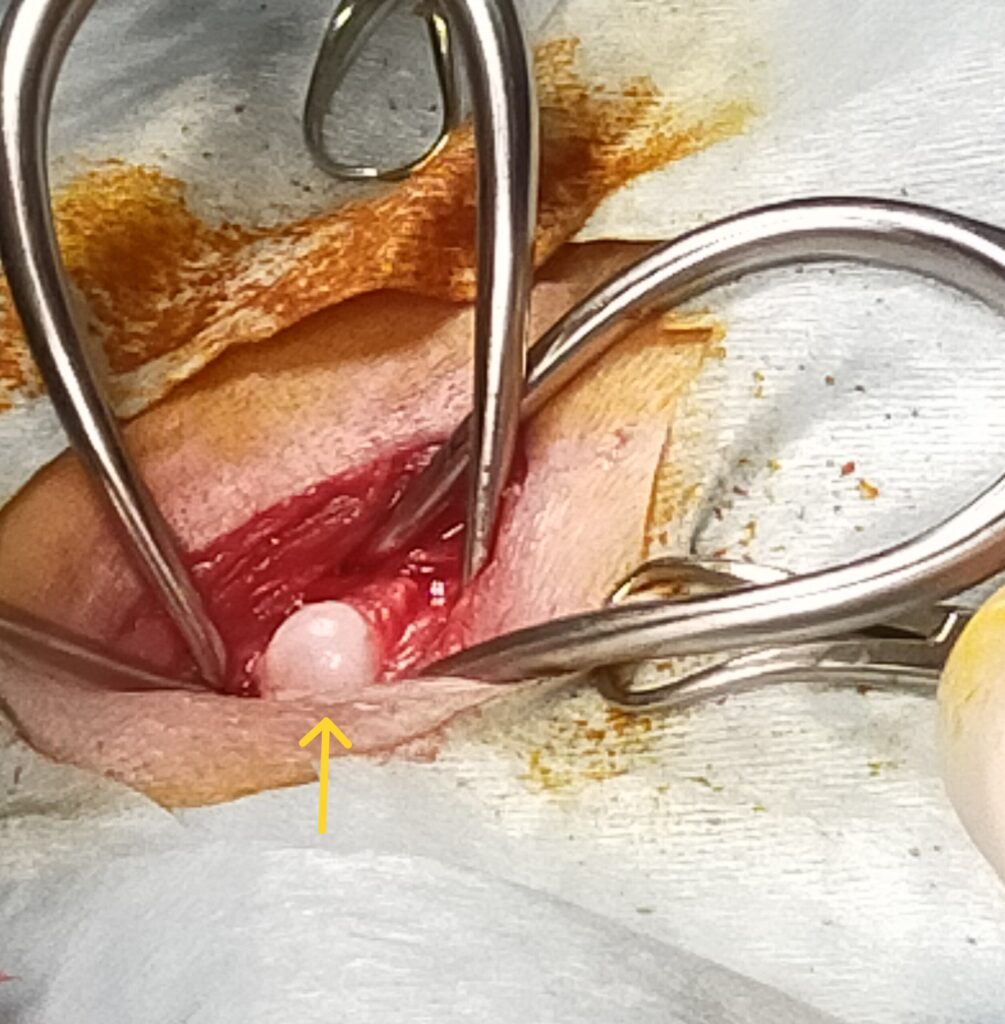

写真下 手術所見(内側アプローチ) 矢印:露出した大腿骨頭部

当院では骨頭切除の手術を内側(内股)から行うことで、筋肉や靭帯・関節包という大切な組織をそのまま温存することにより外側からの手術法に比べて圧倒的に術後の改善が早くみられます。